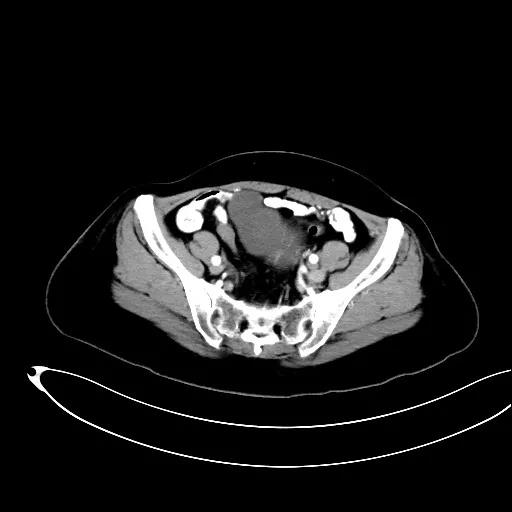

某患者因为“腹痛1周”而入院,外院B超提示子宫上方囊实性肿物,CT提示:左侧附件区占位,并盆腔及腹主动脉旁淋巴结转移。右肾动脉有右肾动脉及异位右肾动脉,其下均有肿大淋巴结。

排除禁忌后,在全麻下行“次广泛子宫切除+双附件切除+大网膜切除+阑尾切除术+盆腔淋巴结及腹主动脉旁淋巴结切除术”。术中切除腹主动脉左旁、右旁及后方淋巴结,达左右肾动静脉水平。多个淋巴结呈融合状态,长径约3-5cm。手术由陈亮副主任医师和宋趣清主治医师完成。

妇科一病区严格遵循指南推荐,在影像学或探查淋巴结阳性的晚期卵巢癌中,若能达到满意减瘤,仍常规行盆腔及腹主动脉旁肿大淋巴结切除/清扫术(如下图举例)。通过前期初步统计分析,肠系膜下动脉至肾静脉下淋巴结转移阳性率为25%左右,在全部腹主动脉旁淋巴结转移患者中约占30%,显示了肾静脉下腹主动脉旁淋巴结清扫的价值。其对生存的影响有待进一步观察。